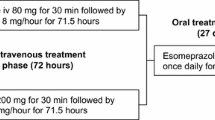

After successful endoscopic haemostasis, patients received either highdose IV esomeprazole (80mg infusion over 30 min, then 8mg/hour for 71.5 hours) or no-IV esomeprazole treatment, with both groups receiving oral esomeprazole 40mg once daily from days 4 to 30.